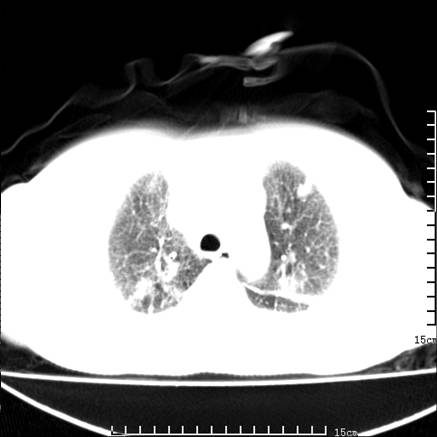

女,王某,58岁,咳嗽三个月余,基层医院二个月前诊为肺结核,用抗结核药二个月无明显疗效。

心包积液致肺瘀血.右侧周围型肺癌伴肺内转移,中间裂积液,叶间胸膜肥厚.右上肺大泡,右侧胸膜肥厚.

双肺继发型tb,心功能不全并肺淤血、心包、双侧叶间裂积液,肺大泡,右下胸膜肥厚钙化。

肺窗真难看,建议重做!